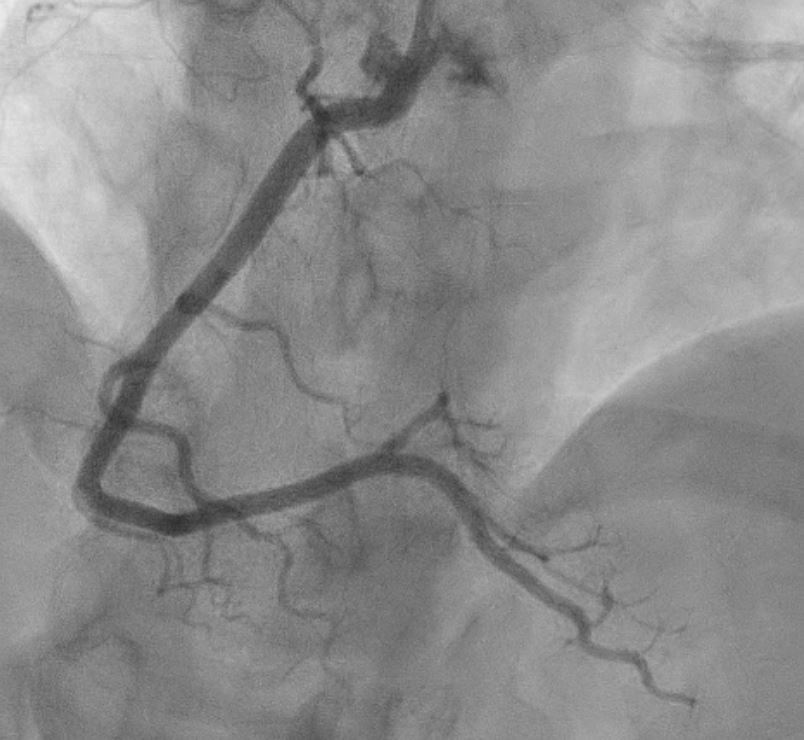

Proceeded with Primary PCI that revealed normal coronaries with mid LAD myocardial bridging . ST elevation resolved in cath lab.